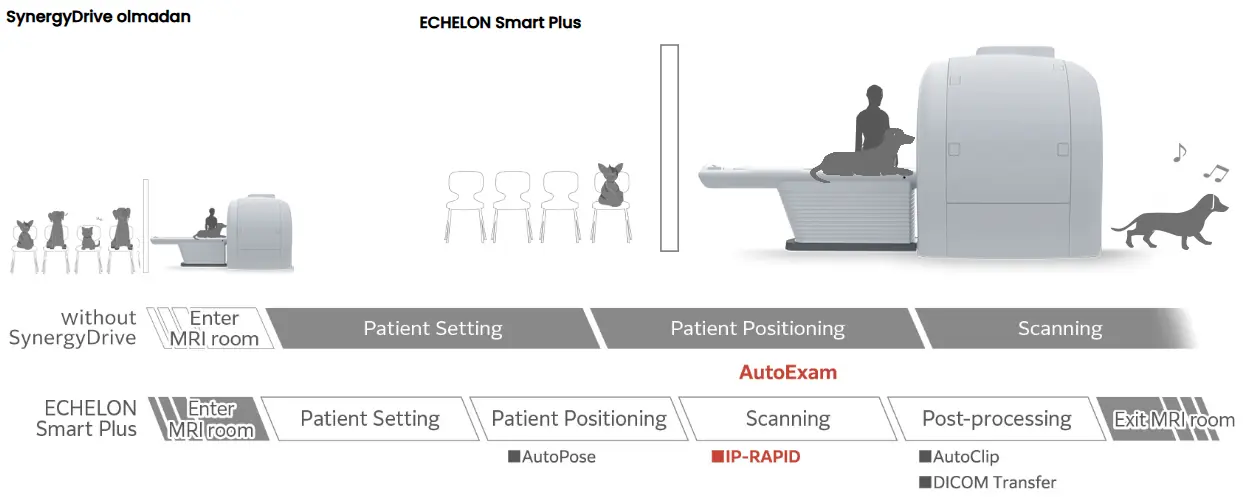

IP-RAPID, geleneksel görüntüleme yöntemleriyle karşılaştırıldığında, görüntü kalitesini korurken tarama sürelerini %60`a kadar azaltan, iteratif işleme kullanan bir yüksek hızlı görüntüleme teknolojisidir.

Konumlandırma, görüntüleme ve çekim sonrası işleme işlemlerinin tamamı tek bir adımda tamamlanır. İnceleme süresi, işlemlerin basitleştirilmesi sayesinde kısalır.